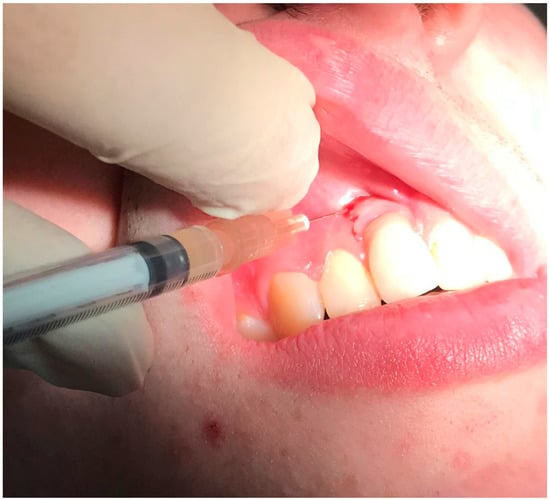

Figure 3.

Application of antibiotics with special device around dental implants in positions 3.2 and 4.2.

Before considering performing one surgical procedure in order to treat the pathology (by regenerative or resective surgery), the authors decided to perform nonsurgical treatment, following the patient’s will (who rejected the surgical treatment for the first instance) and to evaluate the results over time, with particular attention to the soft tissue healing following the treatment. We proposed the use of topical applications of 14% doxycycline (Ligosan®, Kulzer, Hanau, Germany). We performed two professional treatments in two visits within 1 week. After local anesthesia with articaine 4% and epinephrine 1:200,000, the antibiotic was placed directly into the pocket with a specific device. The injection was given gently, with a specific and dedicated sterilized device, until we clearly visualized the antibiotic spilling outside of the pocket after filling it completely (Figure 3). After cleaning the surface of the abutments from the residues of the antibiotic, the prosthesis was screwed again. The patient was instructed to avoid any trauma involving the peri-implant mucosa and to rinse with 15 mL 0.2% chlorhexidine twice a day for 7 days after each treatment.